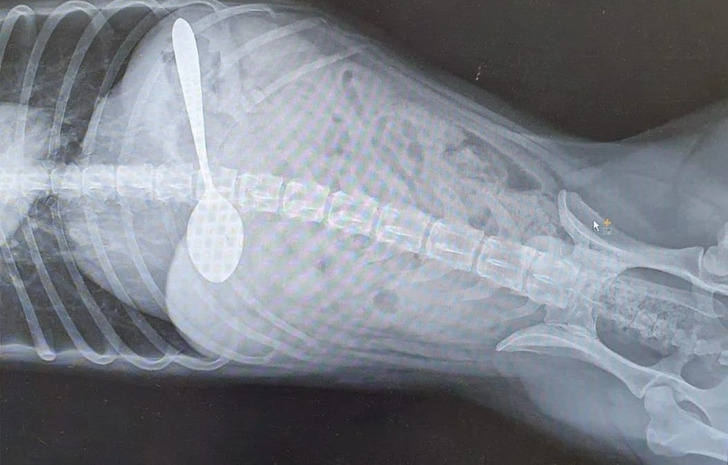

8. „Донесоа кученце кое чудно одеше“